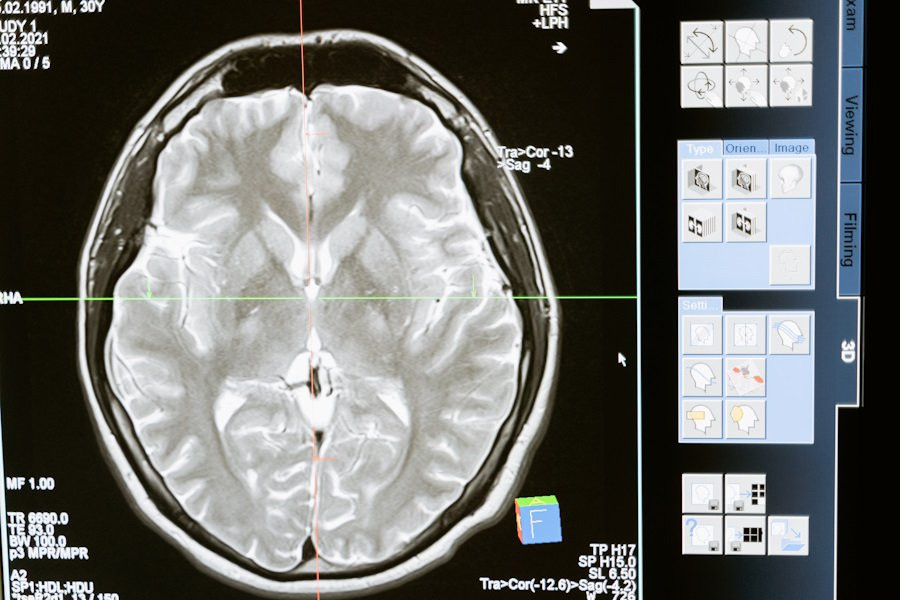

Исследователи из Kyushu University (Япония) сделали важный шаг в лечении рассеянного склероза (РС), серьезного заболевания, поражающего центральную нервную систему. В исследовании, опубликованном на портале Scientific Reports, команда выявила новую терапевтическую цель для лечения РС на поздних стадиях.